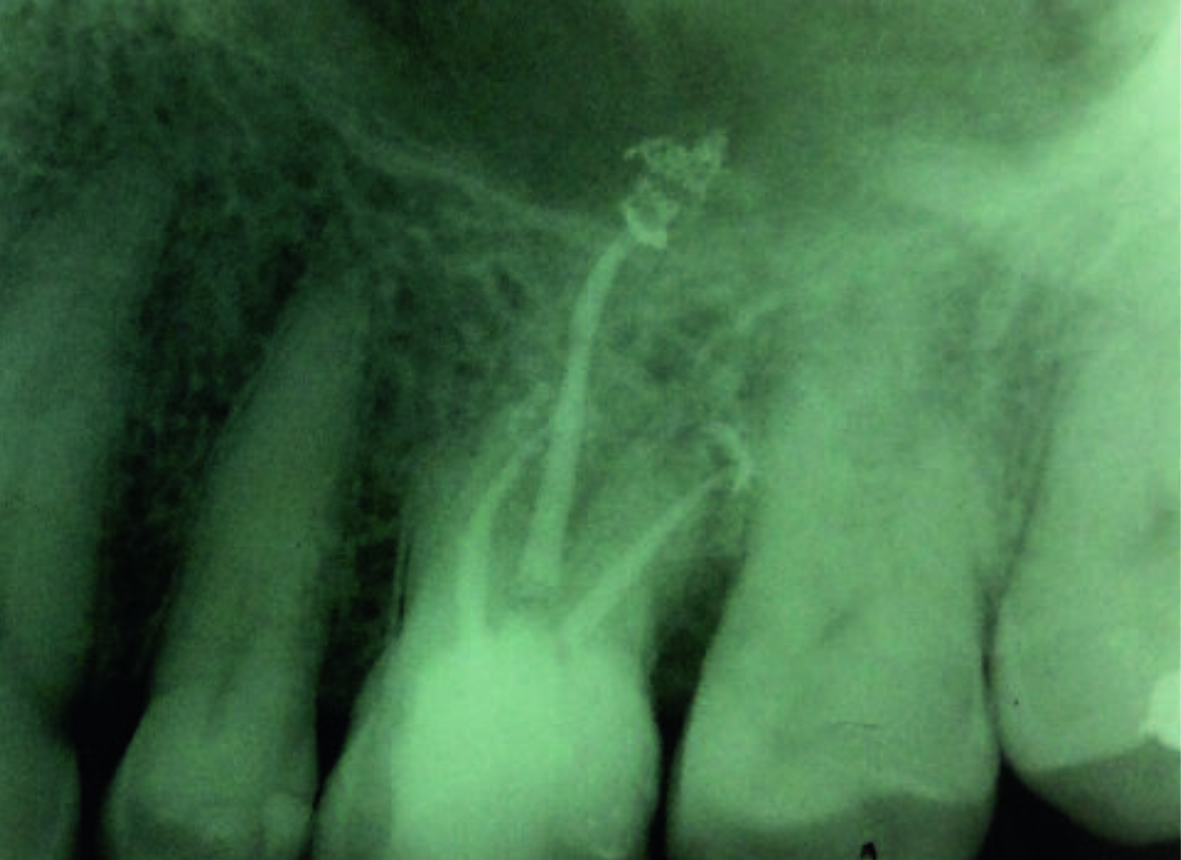

конденсації (Фото

8). Встановили подвійну тимчасову пломбу зі сульфату кальцію та склоіономера,

після чого пацієнта направили до його лікаря для встановлення постійної

реставрації.

Фото 8. Рентгенограма, зроблена після лікування.